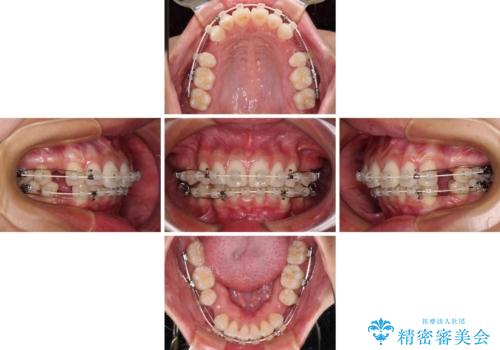

- 矯正装置

- 審美装置

- 飛び出した前歯を気にして来院された患者様です。

口元を引っ込めるために上下左右の第一小臼歯4本を抜歯することとしました。

結婚式を行う予定があるとのことで、表側のワイヤー装置で、速やかに治療を終えられるようにしました。